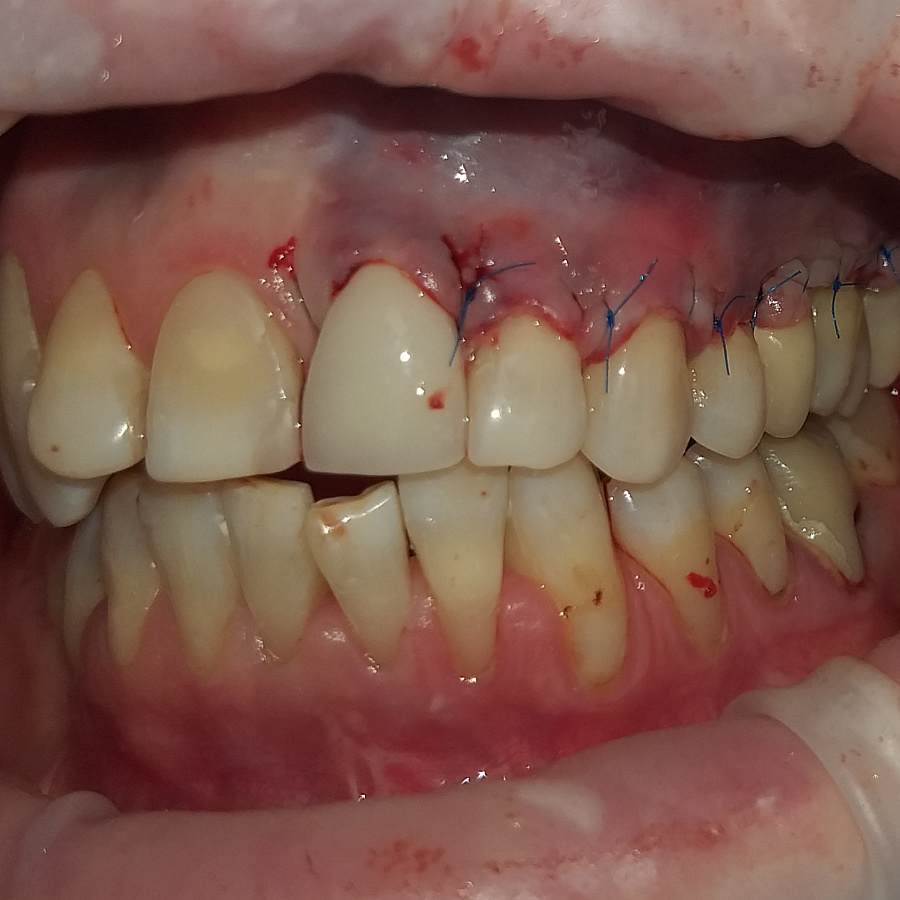

Операция по закрытию рецессии десны мягкими тканями - перемещение полнослойного слизистого лоскутка. Операцию проводил хирург Денис Черкашин.